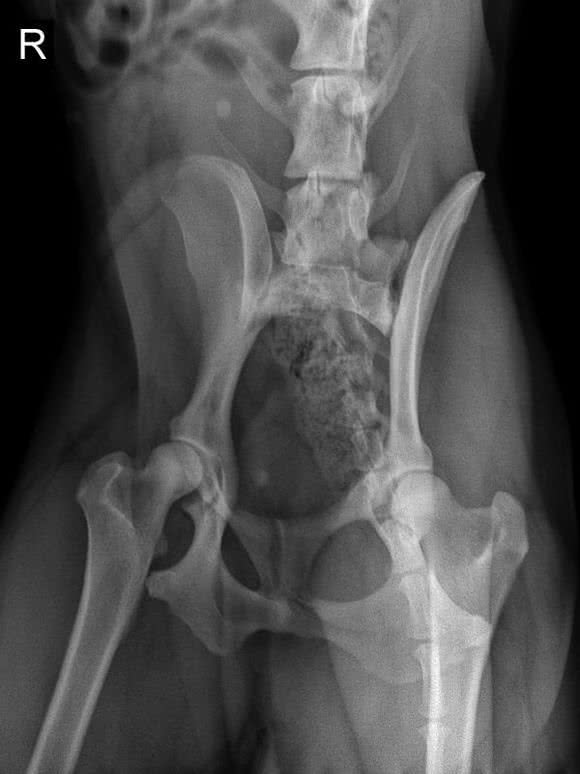

不过网友家的阿拉斯加最近好像有点异常,总是坐在地上就开始大叫,叫声既凄厉又尖锐,特别难受!

这可把铲屎官给吓坏了,以为狗狗在叫什么,家里都检查了一遍也没有什么危害,最好只好带去了检查。

可是这一检查就了不得了,这查出来居然说是狗狗太胖了,挤压到了背部脊椎神经,所以才感到痛苦,需要开始给狗狗节食减肥了!